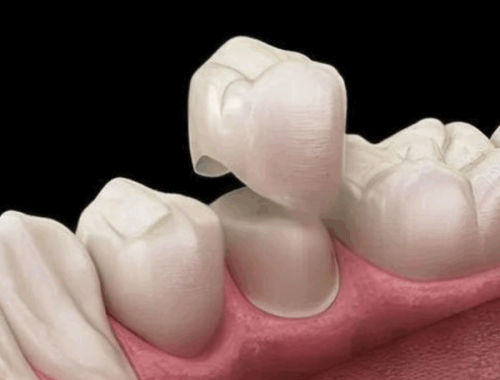

| 项目 | 价格 |

|---|---|

| 补牙 | 200 - 500 元 |

| 牙齿矫正 | 8000 - 20000 元 |

| 种植牙 | 5000 - 15000 元 |

这样的价格在上海的口腔诊所中具有特别高的性价比,让患者不用为高昂的治疗费用而焦虑。